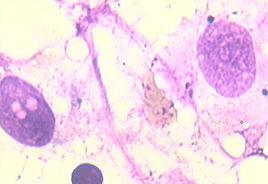

(3)骨髓象:

①3系或2系減少,至少1個部位增生不良,巨核細胞明顯減少;②骨髓小粒中非造血細胞及脂肪細胞增加。